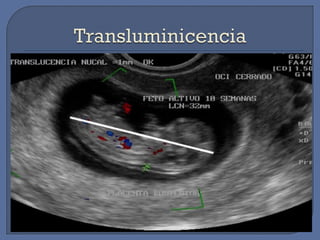

RECONOCIMIENTO ECOGRAFICO

VAGINAL

SACO GESTACIONALSACO GESTACIONAL 16 días después de la ovulación16 días después de la ovulación

10 días después de la implantación.10 días después de la implantación.

CAVIDAD CORIONICACAVIDAD CORIONICA 2 semanas después de la concepción2 semanas después de la concepción

SACO VITELINOSACO VITELINO 3 semanas3 semanas

ACTIVIDAD CARDIACAACTIVIDAD CARDIACA 4 semanas post-concepción4 semanas post-concepción

 Entre la 5ta-7ma semana del embarazo, el

usg transvaginal revelará el saco

gestacional, saco vitelino y el embrión.

 Durante la 6ta semana aparece el saco

vitelino, que posee una estructura

redonda dentro del saco gestacional.

Por F.U.R segura y confiable.

Por Ecografía precoz:

LCN ( 7 - 12 sem ) EG + 5 días 3.5

Femúr ( 12 – 22 sem ) EG + 7 días + / -

DBP ( 12 - 22 sem ) EG + 10 días 7 días